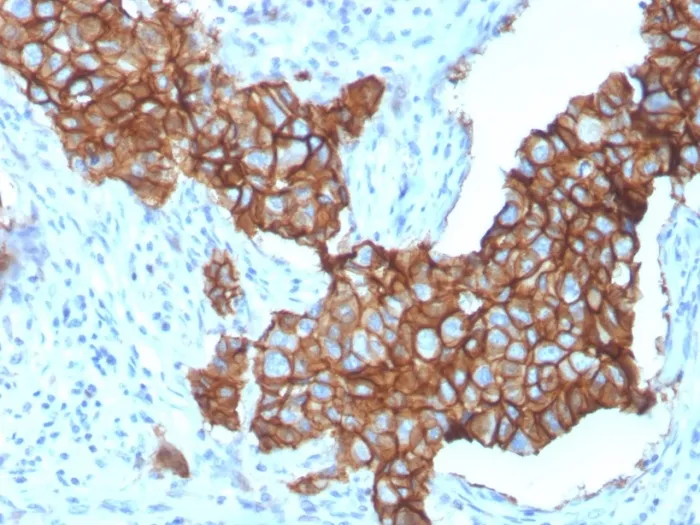

- Description: Recognizes a protein of 185 kDa, which is identified as c-erbB-2/HER-2/neu. Its epitope is localized in the extracellular domain. C-erbB-2/HER-2 is a member of the EGFR family. This MAb is specific and shows minimal cross-reaction with other members of the EGFR-family. Receptors of this family are located on the plasma membrane and consist of an extracellular ligand-binding domain that is connected to a large intracellular domain by a single transmembrane sequence. c-erbB-2/HER-2 protein is over-expressed in a variety of carcinomas especially those of breast and ovary. Primary antibodies are available purified, or with a selection of fluorescent CF® Dyes and other labels. CF® Dyes offer exceptional brightness and photostability. Note: Conjugates of blue fluorescent dyes like CF®405S and CF®405M are not recommended for detecting low abundance targets, because blue dyes have lower fluorescence and can give higher non-specific background than other dye colors.

- Applications: Flow (verified) | IHC, FFPE (verified)

- Positive Control: SKBR-3 cells. Human breast carcinoma tissue (IHC).